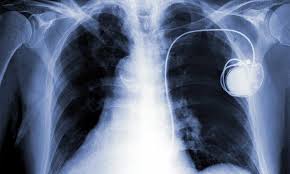

External defibrillation may still be necessary for a person with a pacemaker.

Cpr is performed exactly the same on a person with an implanted pacemaker as on someone without out. If you need to defibrillate a person with a pacemaker it is important to place the pads at least one inch either side of the device. Can you use an aed on a person with a pacemaker. Don t worry about damaging the device most are designed to withstand external defibrillation and saving the victims life is much more important than saving a machine.

Make sure their skin is dry shave off excessive hair and remove medicinal patches if any. It is also possible for a pacemaker to malfunction failing to deliver the lifesaving intervention. Set up the aed machine for use or ask someone to assist so you do not stop the cpr process. So can you use an aed on someone with a pacemaker.

However thankfully aeds are absolutely safe to use on someone with a pacemaker. Aed pads should always be placed on the upper right and lower left portions of the victim s chest surrounding the heart. In order to use the aed on somebody with a pacemaker you need to do the following.Source : pinterest.com